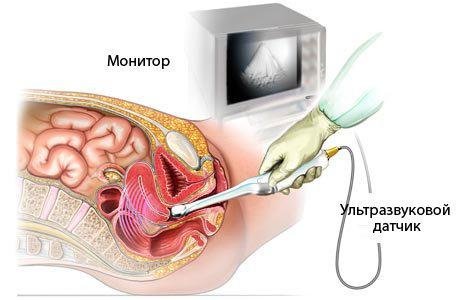

- трансабдомінальне. Датчик прикріплюють до шкіри живота (над лобком). Сигнал проходить через передню черевну стінку.

- вагінальне. Датчик вводять безпосередньо в піхву, від зародка його відокремлює лише стінка матки. Його часто призначають пацієнткам із зайвою вагою.

- комбіноване. Якщо картина незрозуміла, то трансабдомальное і вагінальне УЗД поєднують.